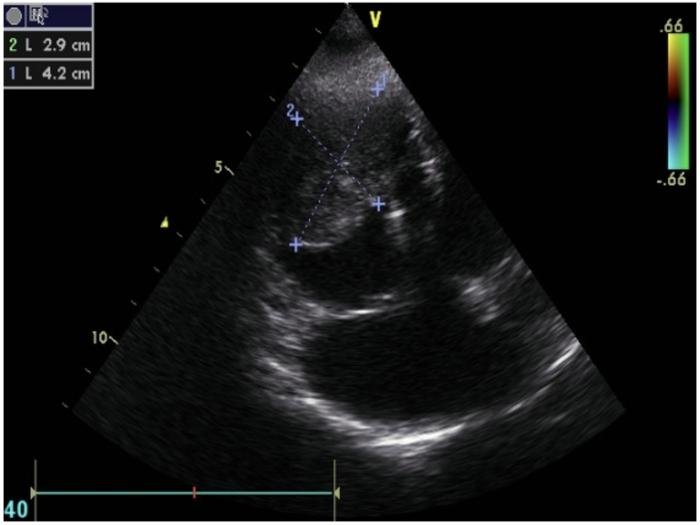

Durante la exploración física general el único hallazgo relevante es la presencia de un soplo mitral y una frecuencia cardiaca de 140 lpm. La ecocardiografíaconfirma la presencia de una masa en el ventrículo derecho (3.8 × 5 cm) (Figura 2 y 3), junto con insuficiencia mitral en estadio B2 e hipertensión pulmonar (consenso ACVIM). Se instaura terapia con clopidogrel (1.5mg/kg/día), para la prevención de tromboembolismo, y se sustituye el benaceprilo por pimobendan (0.5 mg/kg/12 h).

Se propone como diagnósticos diferenciales la presencia de un tumor cardíaco primario vs. metastásico, y se programa una tomografía computarizada (TC) toracoabdominal, para realizar estadio clínico completo, junto con una punción con aguja fina (PAF) de la masa intracardíaca, con el objetivo de obtener un diagnóstico presuntivo (Figura 4). Se añade cimicoxib (2 mg/kg/día) y toceranib fosfato (2.75 mg/kg, lunes-miércoles-viernes) hasta la obtención de los resultados. En la TC se confirma la presencia de neoplasia cardíaca primaria y la citología resulta compatible con un sarcoma, posiblemente un rabdomiosarcoma (RMS).